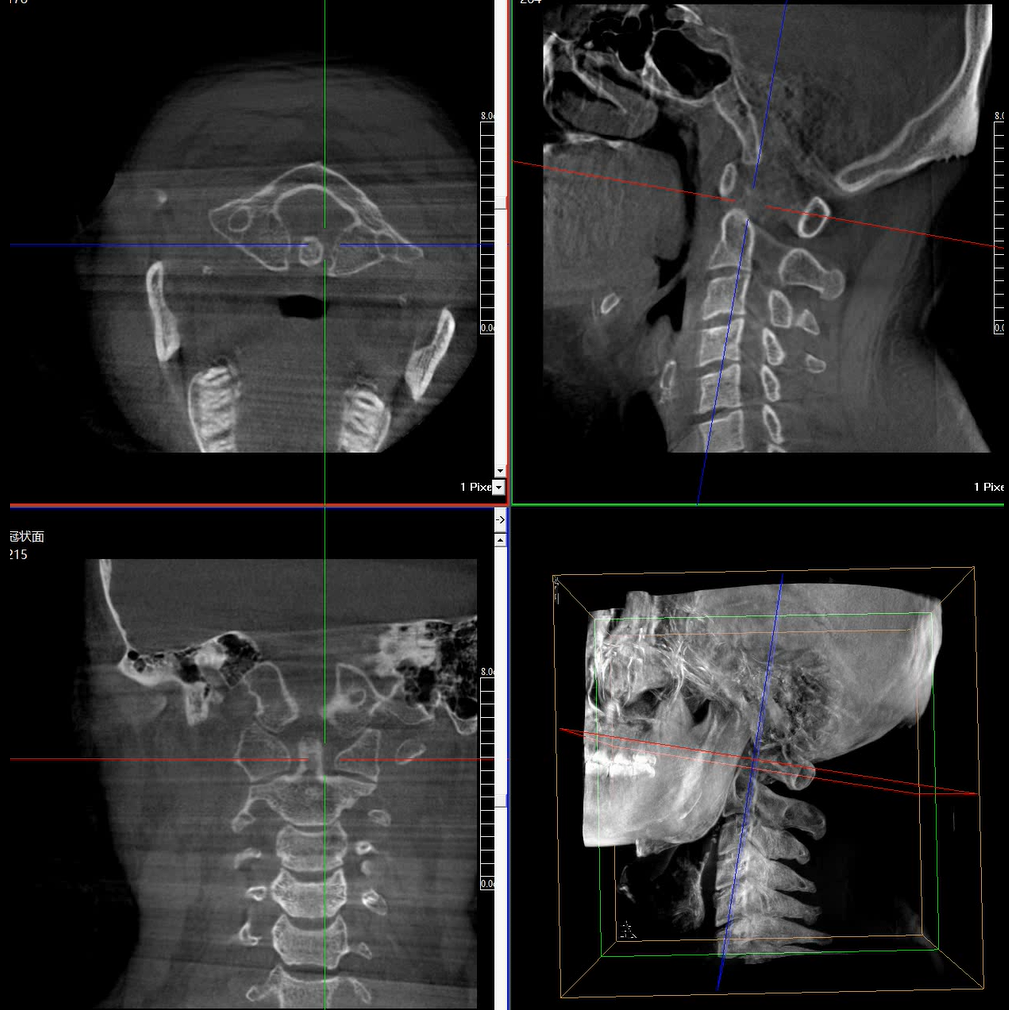

術中三維成像和橫斷面圖像提供多角度的手術診斷信息,輔助醫生進行術中評估判斷,諸如骨折復位情況和內植入螺釘的尺寸和位置,輔助手術更好地完成。

提供更大的術中三維成像視野,采集更多圖像信息,可一次拍全全段頸椎、全段腰椎、七節胸椎、雙側骶髂關節、股骨頭及單側盆骨。